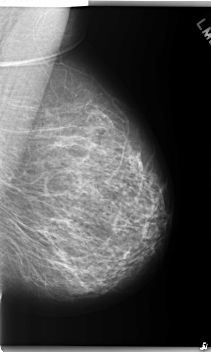

C_0240_1.LEFT_CC

LEFT_CC LINES 5984 PIXELS_PER_LINE 3752 BITS_PER_PIXEL 12 RESOLUTION 50 NON_OVERLAY